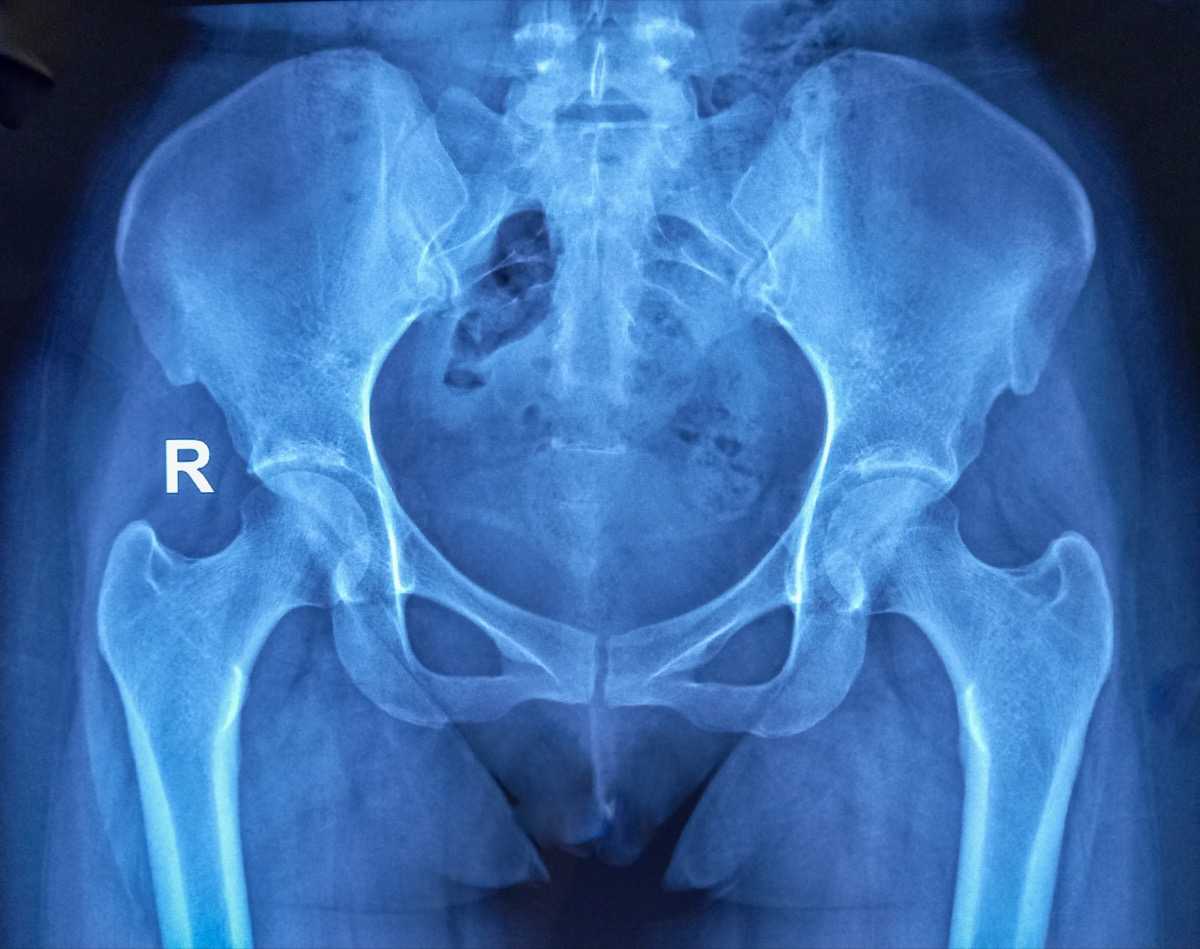

In 2025, Montefiore Einstein’s Department of Obstetrics & Gynecology & Women’s Health expanded multidisciplinary high-risk services, scaled minimally invasive surgical capacity, and continued robust clinical and translational research — while maintaining a sustained commitment to equitable, patient-centered care across the Bronx, Westchester, and the Hudson Valley.

Minimally invasive and robotic procedures